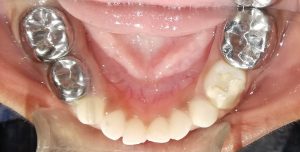

We at the Department of Pediatric & Preventive Dentistry focus on comprehensive oral health care needs of a child from infancy to adulthood and provide comprehensive, therapeutic as well as preventive care to all children including those with special care needs.

Treatment and Services